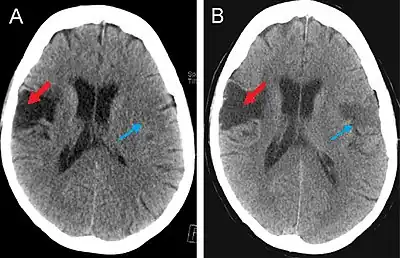

(A) CT scan of a patient with middle cerebral artery stroke illustrating hypodensity areas within the temporal and frontal lobes. (B) CT scan displaying an ischemic stroke bordering the fronto-parietal opercular cortex (red arrow) and a left-sided ichemic lesion of the fronto-parietal opercular cortex (blue arrow).

CT Scan

This computer-tomography type of imaging is one of the most used in any clinical environment and although it can detect some of the brain areas affected by a stroke or a trauma it does not provide the same acuity as the magnetic resonance imaging. CT scans can also reveal, in patients with the syndrome, the bilateral cortical infarcts located in the posterior frontal region involving the opercular areas.[3]